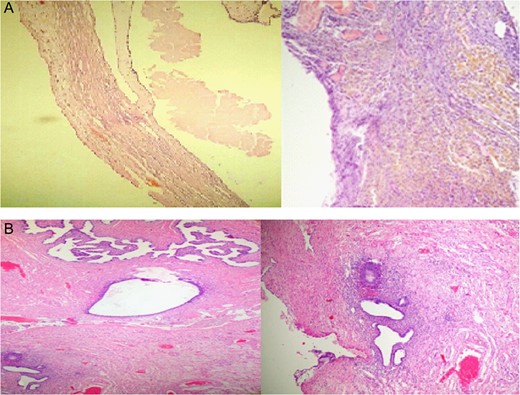

The final pathological results were serous cystadenoma, hyalinized and necrotic with foci of endometriosis measuring 15 × 10 × 7 cm, leiomyoma measuring 1.5 × 1.3 × 1 cm (Fig. 3)

Pathological study after surgery assured that neither thyroid tissue nor teratogenic tissues were found in the specimen and the final pathology diagnosis was serous cystadenoma, endometriosis cyst and leiomyoma.